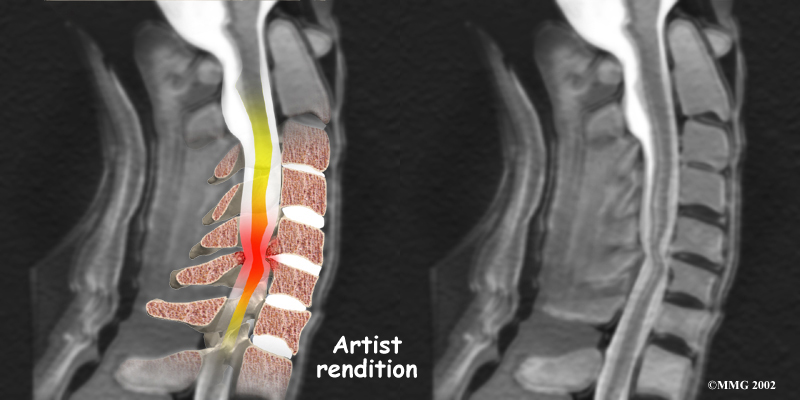

The nucleus may push through the weakened and torn annulus and into the spinal canal. This is called a herniated or ruptured disc. The disc material that squeezes out can press against the spinal nerves. The disc also emits enzymes and chemicals that produce inflammation. The combination of pressure on the nerves and inflammation caused by the chemicals released from the disc cause pain.

If the herniated disc material presses against a nerve root it can cause pain, numbness, and weakness in the area the nerve supplies. This condition is called cervical radiculopathy (mentioned earlier). And any time the herniated nucleus contacts tissues outside the damaged annulus, it releases chemicals that cause inflammation and pain. If the nucleus herniates completely through the annulus, it may squeeze against the spinal cord. This causes a condition that is even more serious because it affects all the nerves of the spinal cord. This condition is called cervical myelopathy.

Stenosis means closed in. Spinal stenosis refers to a condition in which the spinal cord is closed in, or compressed, inside the tube of the spinal canal. Spinal stenosis may be caused by degenerative changes, such as bone spurs pushing against the spinal cord within the spinal canal.

Spinal Stenosis

However, stenosis can also develop when a person of any age has a disc herniation that pushes against the spinal canal. When the spinal cord is squeezed in the neck, doctors call the condition cervical myelopathy. This is an alarming condition that demands medical attention. Cervical myelopathy can cause problems with the bowels and bladder, change the way you walk, and affect your ability to use your fingers and hand.